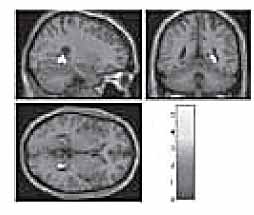

They asked Mr. Gerard Senehi (his brain pictured at right)

“… well known for his abilities to perform various paranormal tasks such as telekinesis, mind reading and telepathy”

“This study’s findings are suggestive of an association between telepathy and the right parahippocampal gyrus.”